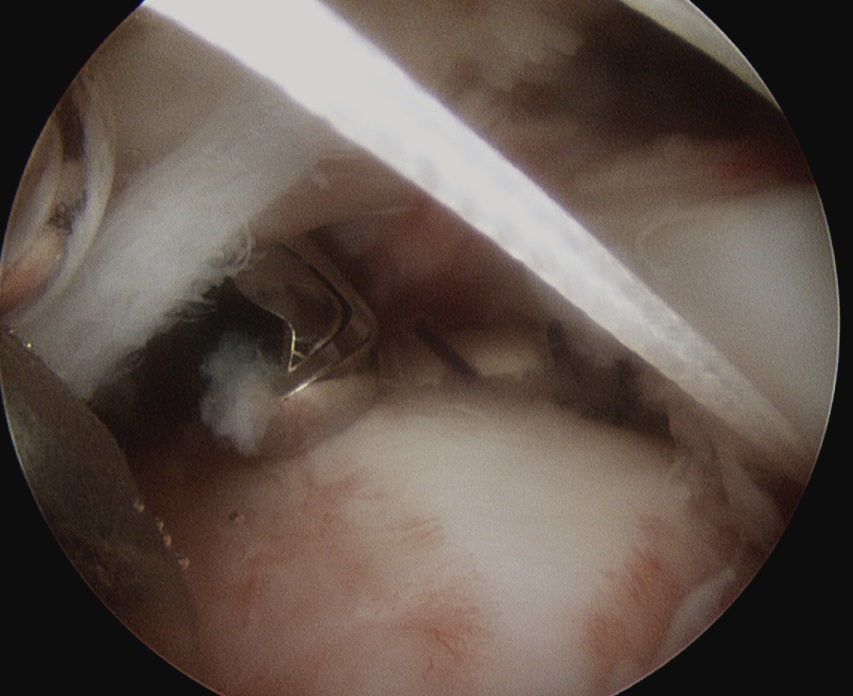

Prepare footprint

- debride

- insert anchors (retract port of Wilminton into subacromial space)

- pass sutures with suture passer

- tie